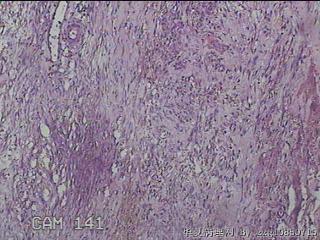

左肘部包块

性别

男

年龄

39

临床诊断

左肘部肿物:炎性脂肪瘤

一般病史

发现左肘部肿物1周。

标本名称

大体所见

灰白粉红色组织2x1.8x0.3㎝一团,表面结节状,光滑,切面灰白粉红色,质软。

图3